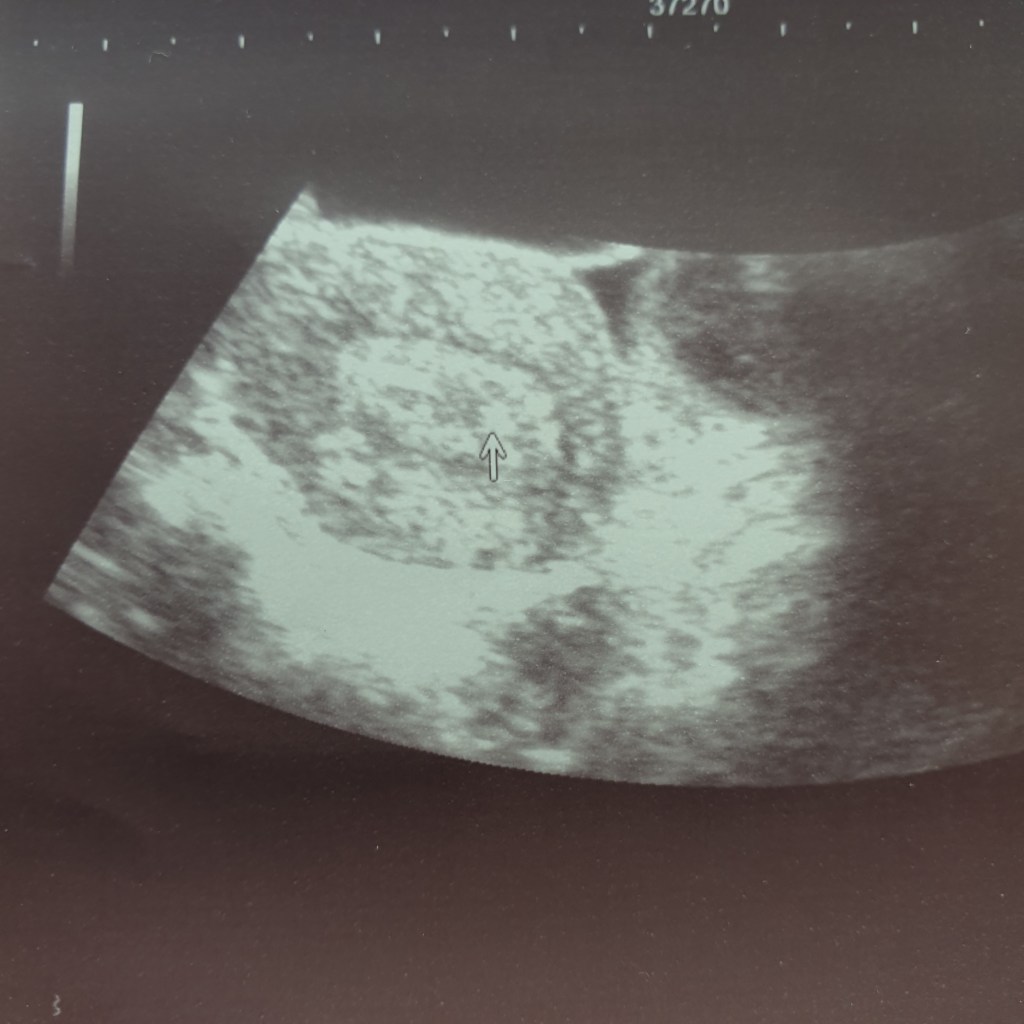

They then stick a catheter up inside me while I have the nurse pushing a medical thing hard onto my stomach so that they can see what’s going on inside….. he is pushing onto my bladder. My extremely full bladder.

Before I know it, I am pregnant.

I AM PREGNANT.